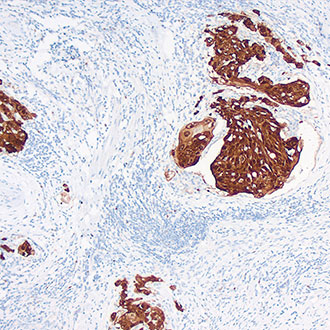

IHC

免疫组织化学(IHC)